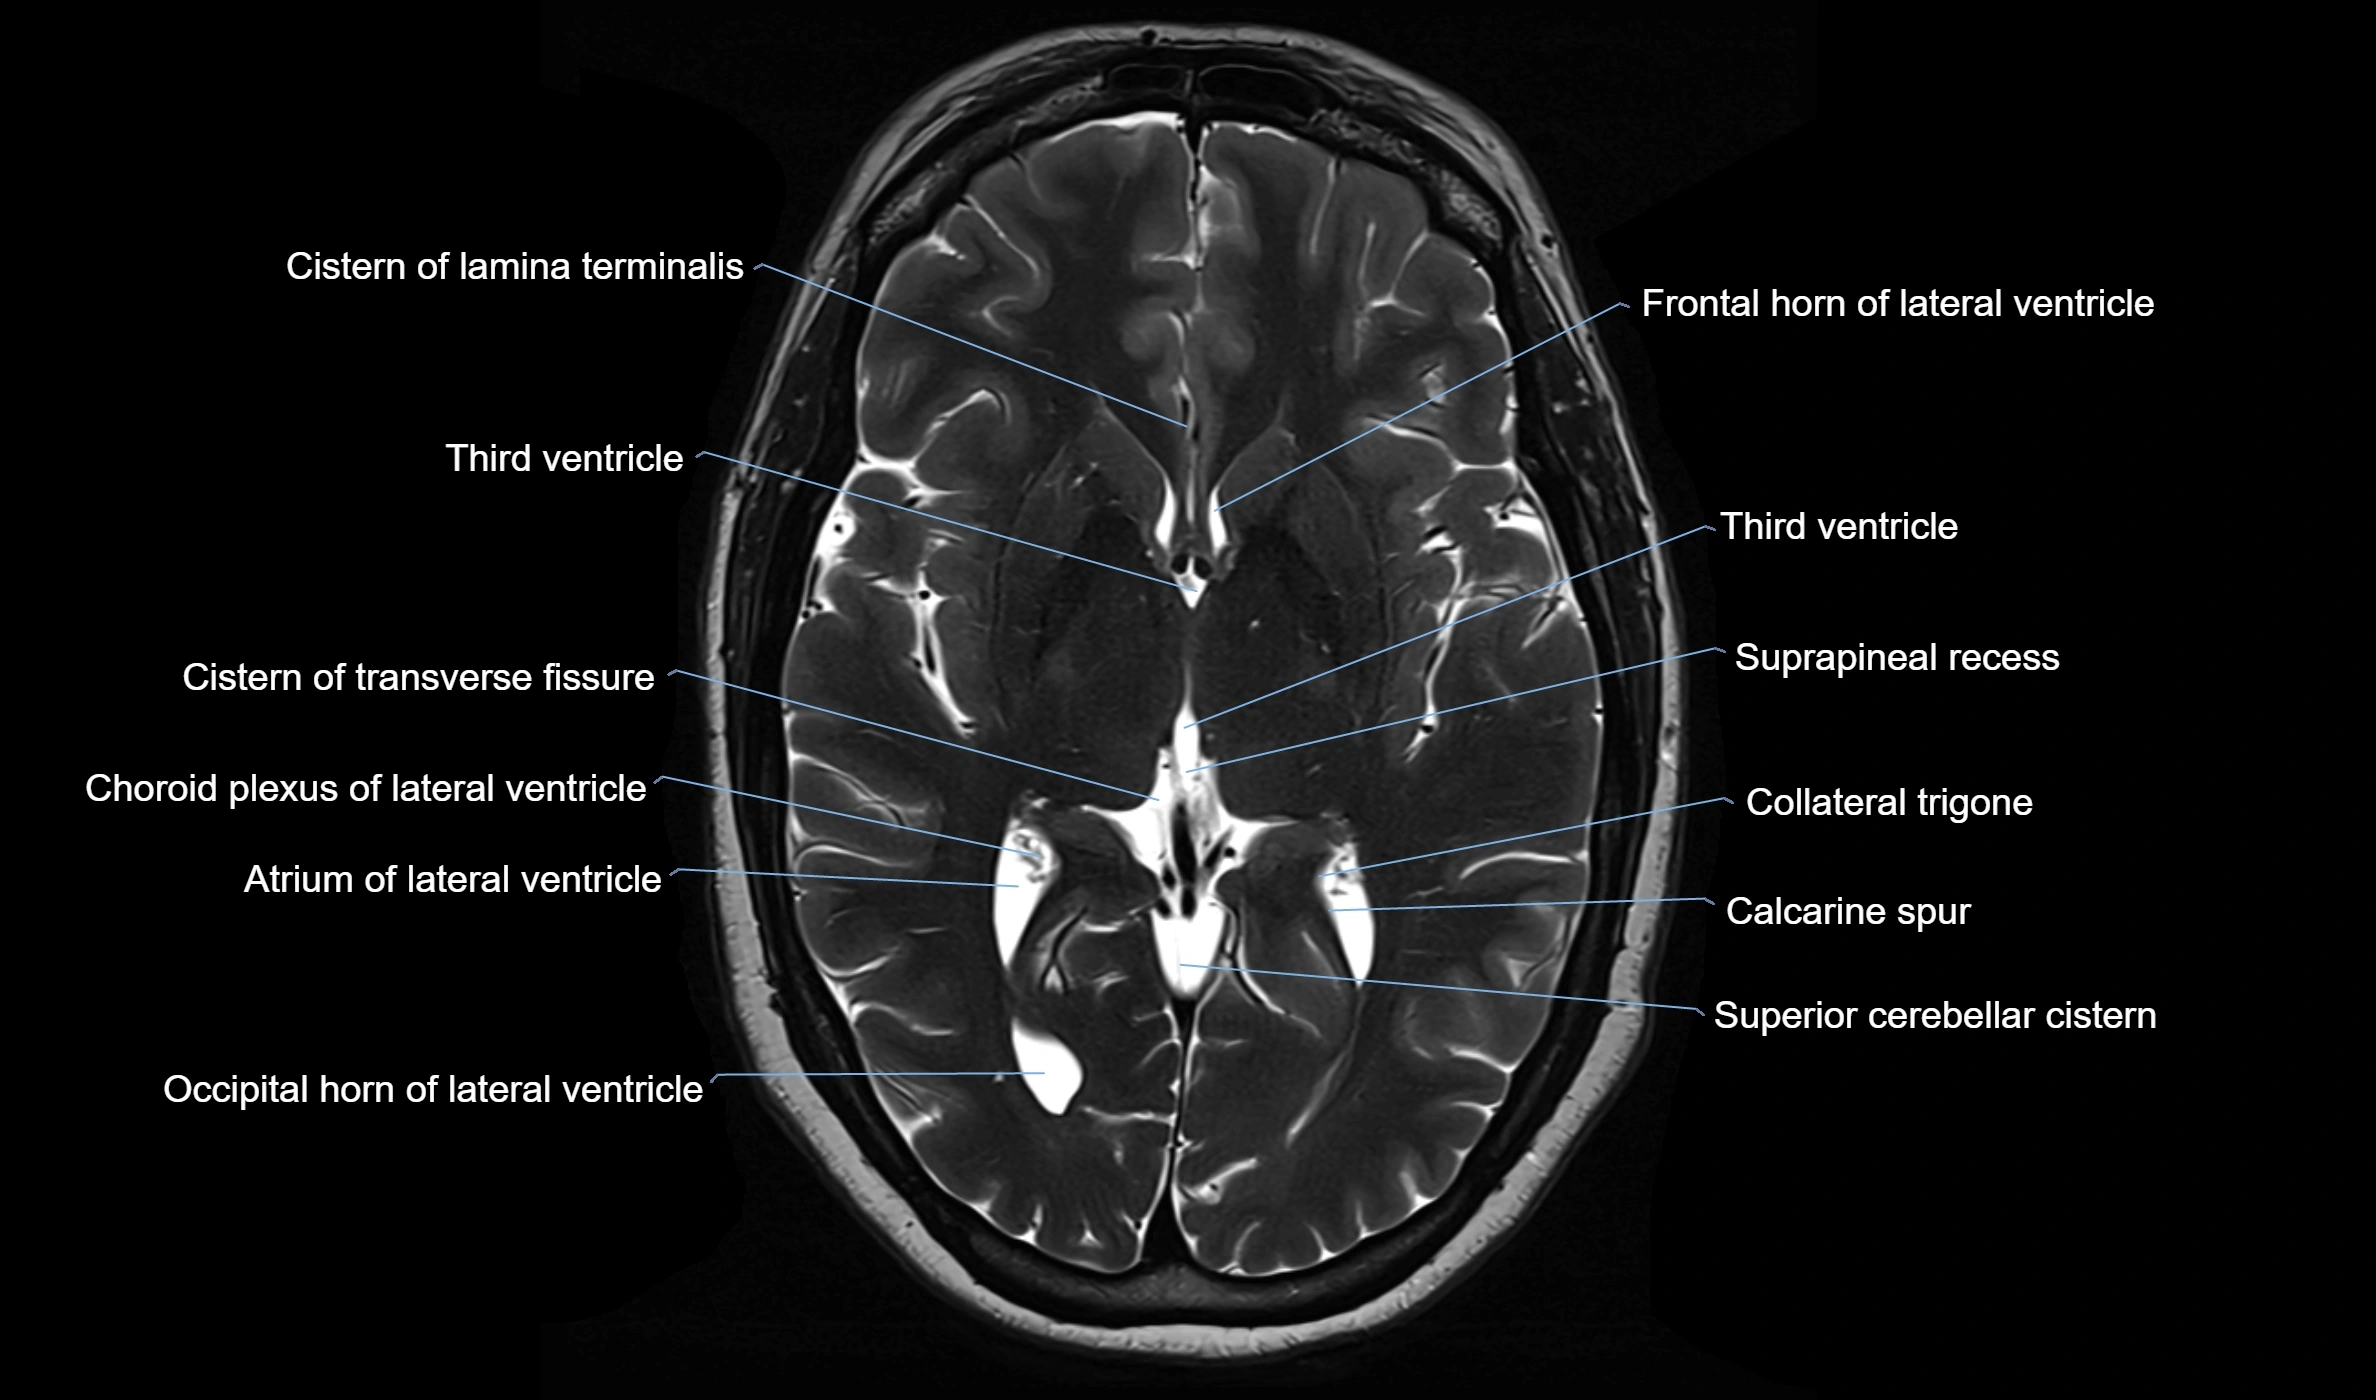

• T2-weighted images:

• The cistern is hyperintense (bright) due to the high water content of CSF.

• Encapsulated vessels and nerves are seen as flow voids or hypointense lines within the bright background.

image